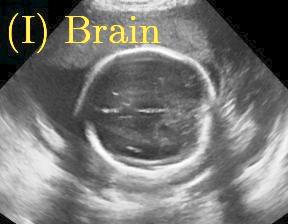

Sound-opaque occluders, including bones and calcified tissues, block the propagation of sound waves by strongly absorbing or reflecting sound waves during scanning. The regions behind these sound-opaque occluders return little to no reflections to the US transducer. Thus these areas have low intensity but very high acoustic impedance gradients at their boundaries (e.g. Fig. 1(a) left column). Reducing acoustic shadows and correct interpretation of images containing shadows rely heavily on sonographer experience. Experienced sonographers avoid shadows by moving the probe to a more preferable viewing direction during scanning or, if no shadow-free viewing direction can be found, a mental map is compounded with iterative acquisitions from different orientations.

We propose a novel method based on convolutional neural networks (CNNs) to automatically estimate pixel-wise confidence maps of acoustic shadows in 2D US images. Our method learns an initial latent space of shadow regions from images consisting of multiple anatomies and with global image-level labels (“has shadow” and “shadow-free”), e.g. Fig. 1(a). The basic latent space is then estimated by learning from fewer images of a single anatomy (fetal brain) with coarse pixel-wise shadow annotations (approximately of the images with global image-level labels), e.g. Fig. 1(b). The resulting latent space is then refined by learning shadow intensity distributions using fetal brain images so that the latent space is suitable for confidence estimation of shadow regions. By using shadow intensity information, our method can detect more shadow regions than the coarse manual segmentation, especially relatively weak shadow regions.

Row I in Fig. 6 shows a fetal brain image from . The confidence estimation of shadow regions from the baseline, the proposed method and the proposedAG method are similarly accurate since we use fetal brain images to train the confidence estimation networks in these three methods. These outperform [16] and [22]. Rows (II-IV) in Fig. 6 show shadow confidence maps of non-brain anatomy from , including lips, abdominal and cardiac. The baseline failed on unseen data during inference. However, the proposed methods are able to generate accurate shadow confidence maps because of the generalized shadow features obtained by the shadow-seg module. Furthermore, the “Lips” example shows that our method is capable of detecting weaker shadow regions that have not been annotated in manual segmentation. This indicates that the confidence estimation network has learned general properties of shadow regions.